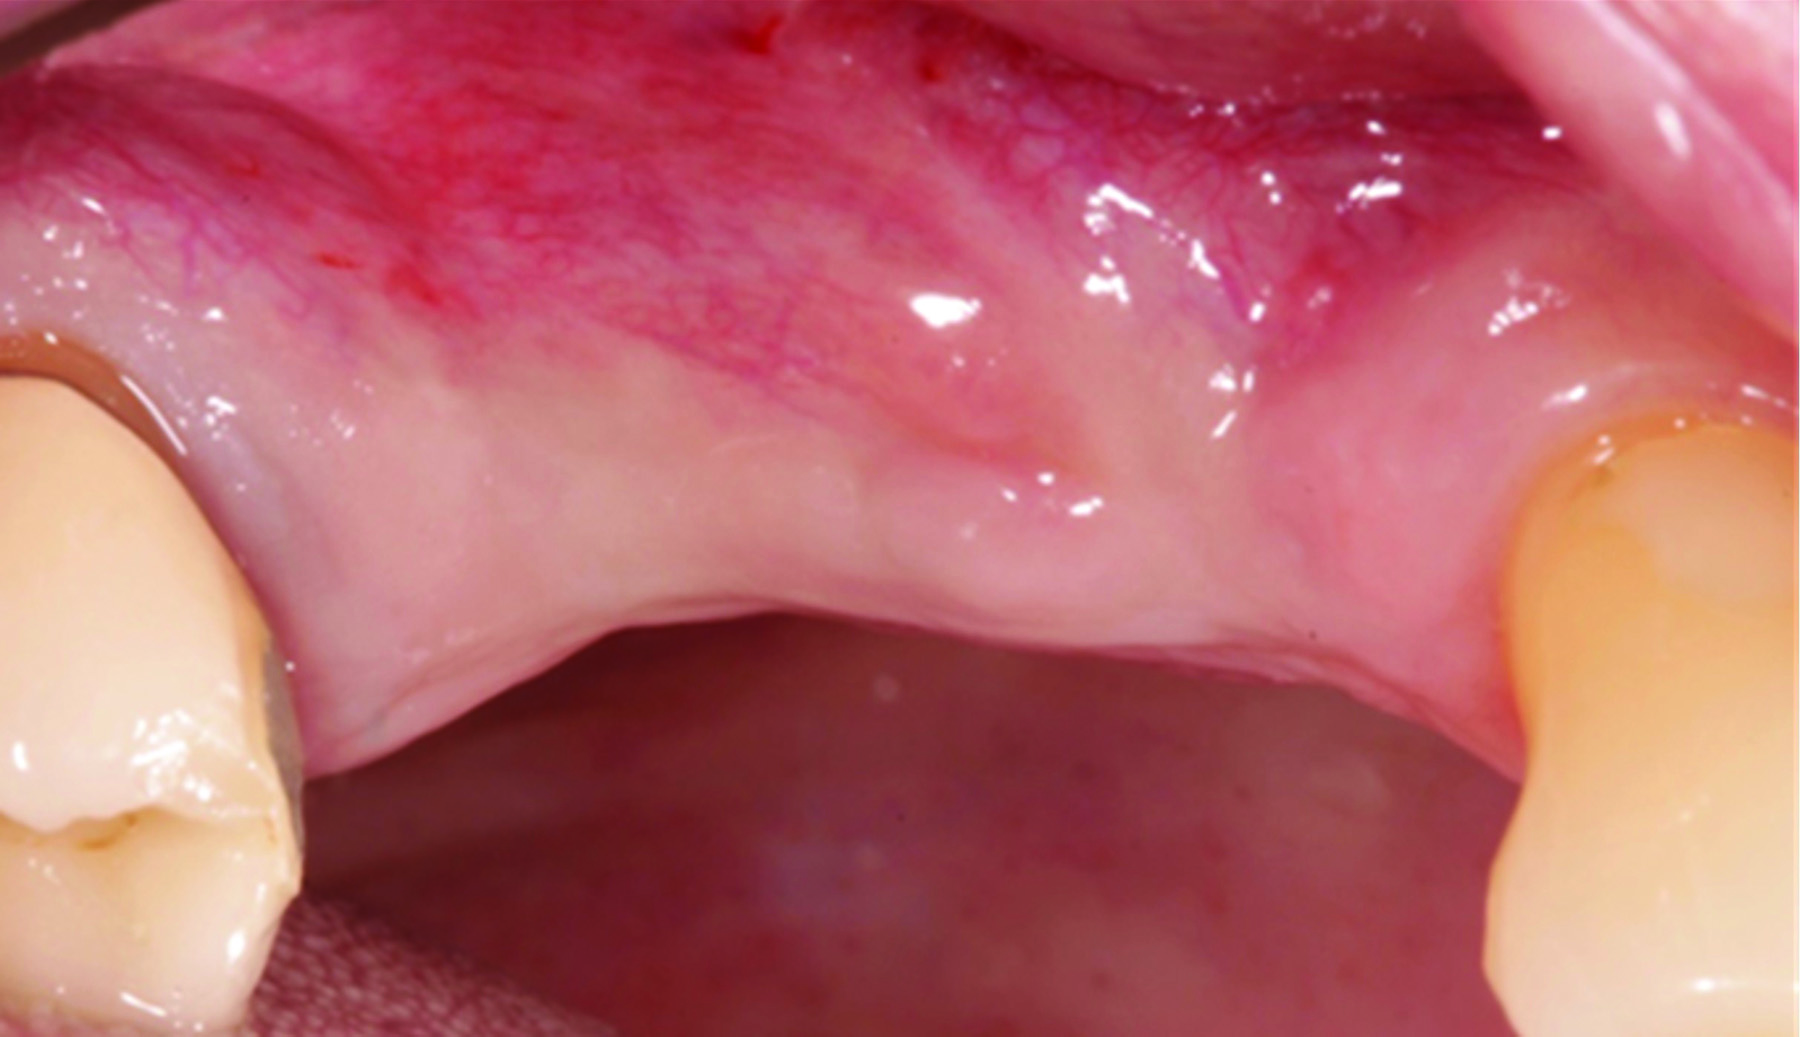

Fig 15 and Fig 16. Example of increasing MT with a CTG. Fig 15: buccal view of initial situation showing deficient mucosal thickness; Fig 16: occlusal view at implant placement with CTG.

Figure 15